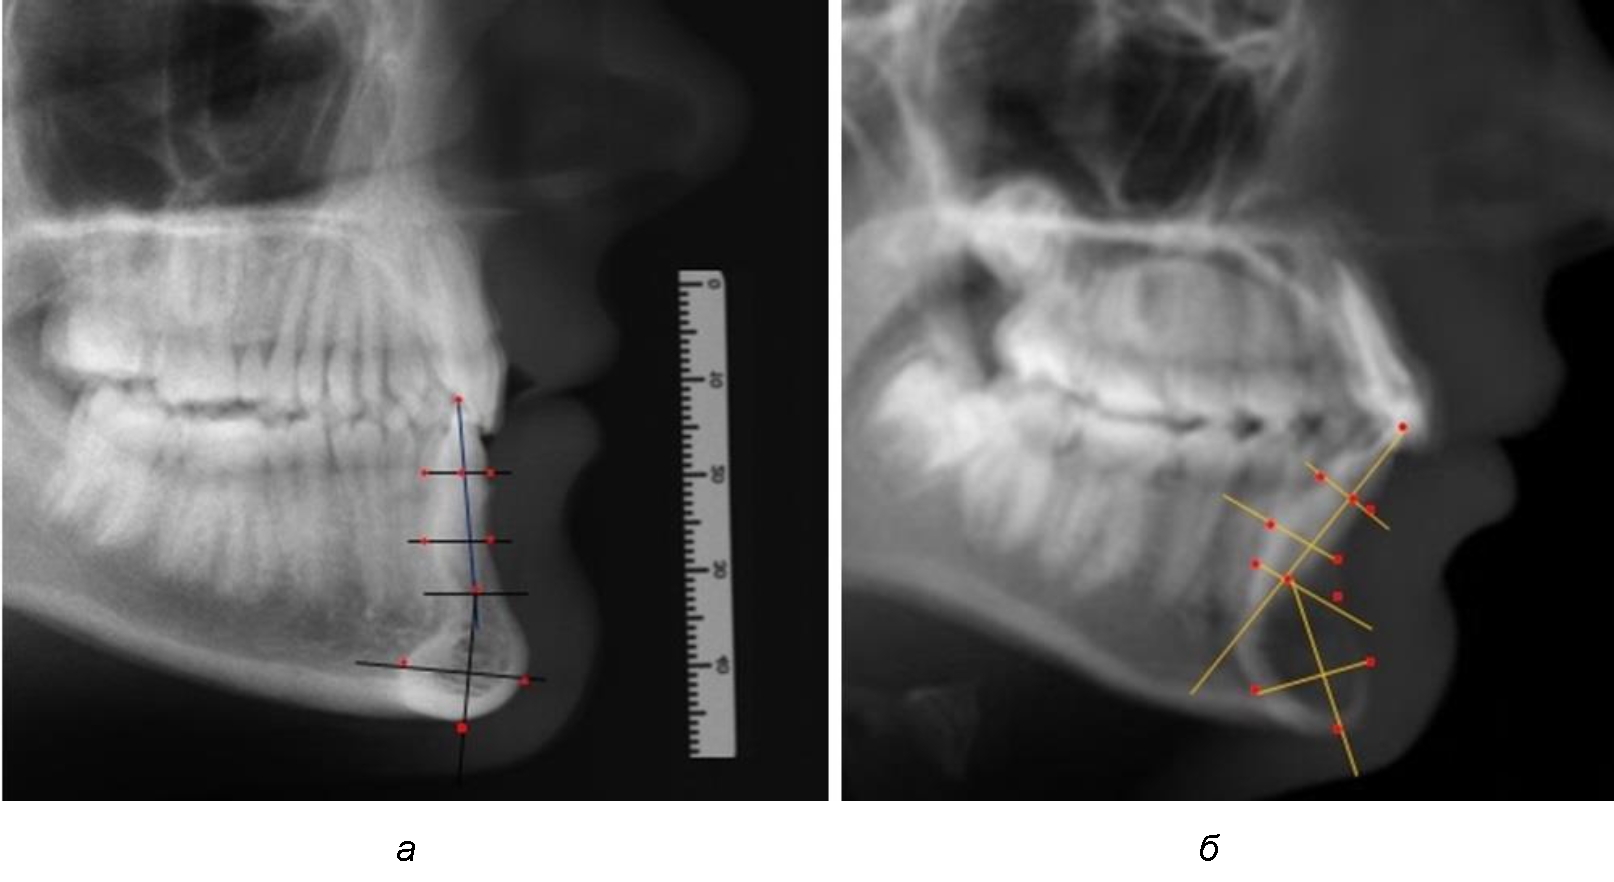

При анализе полученных данных обращает на себя внимание факт того, что из вертикальных параметров зубоальвеолярной части сегмента наиболее вариабельным является размер между апикальными точками Downs и Schwarz (BSM–B), который составлял (6,79 ± 0,54) мм, при величине сигмального отклонения – 2,35. Также большая ошибка репрезентативности и сигмальное отклонение было отмечено при оценки ширины подбородочного выступа. В связи с этим встречались варианты резцовых сегментов нижней челюсти различные как по ширине, так и по высоте, а также по расхождению положения апикальных точек по Downs и Schwarz (рис. 3).

Рис. 3. Варианты среднего (а), широкого (б) и узкого (в) нижнечелюстного резцового сегмента

Варианты резцовых сегментов нижней челюсти различные как по ширине, так и по высоте, а также по расхождению положения апикальных точек по Downs и Schwarz представлены на рис. 4.

Рис. 4. Особенности нижнечелюстного резцового сегмента на ТРГ у людей при среднем (а), широком (б) и узком (в) вариантах